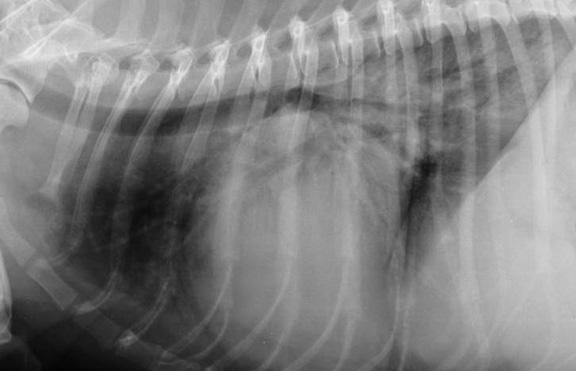

As noted above, what is not visible outwardly, before the dog reaches heart failure, is enlargement of the left chambers of the heart. As greater quantities of blood leak through the damaged mitral valve from the left ventricle back into the left atrium, the thin-walled atrium gradually begins to swell and enlarge (see x-ray image of a severely enlarged left atrium, outlined in red, above) -- called remodeling or cardiomegaly or dilation -- to accommodate the overload of blood, and there is a reduction in the ability of the left ventricle to provide sufficient blood to meet the demands of the rest of the body. The heart then has to pump harder and faster, to meet those demands. The shut-down of the distant blood vessels also has the effect of causing the left ventricle to beat against a higher resistance, causing another increase in mitral valve leakage.

Radiography (x-ray) is used to determine if the heart is enlarged

(particularly the left atrium and left ventricle), if the veins from the

lungs to the heart are distended, or if fluid is beginning to develop in the

lungs.* X-rays also will show any enlargement of

the pulmonary vein, a classic symptom of congestive heart failure (CHF).

• Using radiography to diagnose heart enlargement

Mild to moderate heart enlargement indicates mild to moderate progression of mitral regurgitation (MR), with the heart compensating for the effects of mitral regurgitation by enlarging. Usually the dog displays no outward signs or symptoms of MVD when moderate to severe heart enlargement develops, until the dog reaches the stage of heart failure.

The VHS is not intended to diagnose CHF. It's purpose is to enable veterinarians to more accurately determine enlargement of the heart (called cardiomegaly or dilation) and the progression at which the enlargement is occurring, which usually is due to MVD. However, since MVD normally initially causes only the left atrium (LA) to enlarge, the VHS method is not precise enough to measure only the size of the LA. See for example, the x-ray at left, which shows that the VHS measurements entirely miss the bulbous enlarged LA in the upper right corner of the heart. (Image from Hezzell, 2018.)